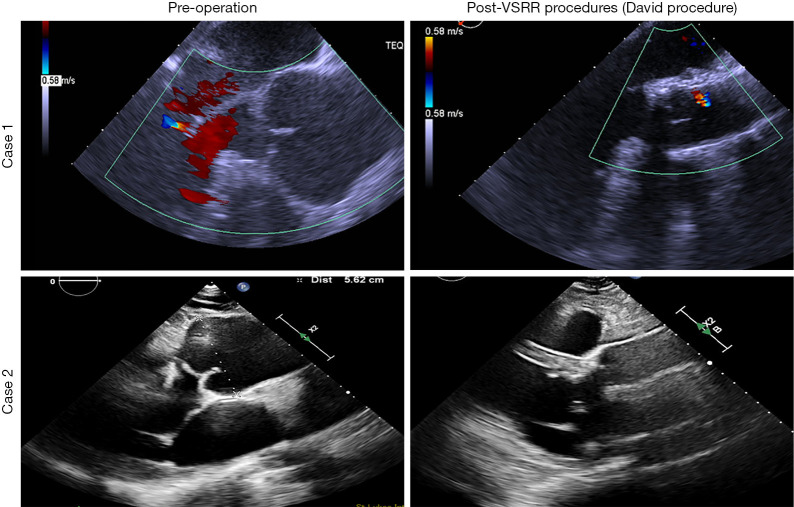

法洛四联症(TOF)是一种经常导致术后主动脉根部长期扩大的疾病。与肺血流相比,主动脉扩张被认为是由主动脉介质的组织学异常和主动脉血流增加的血流动力学特征引起的。严重紫绀、严重右心室流出道(RVOT)梗阻、修复时年龄较大、修复时主动脉尺寸较大以及与主动脉根部长期容量过载相关的主动脉-肺分流术史是报道的危险因素。右主动脉弓、男性和22q11染色体缺失也被报道为危险因素。主动脉根部扩大可引起主动脉反流(AR),导致左心室功能障碍和主动脉夹层风险增加,需要手术干预。主动脉瓣修复治疗AR的结果有所改善,导致选择这种方法的趋势增加,特别是在需要机械瓣膜置换术的年轻患者中,从而避免了抗凝治疗的需要。成人先天性心脏病患者预防性主动脉根置换术的适应症和时机尚未描述,目前的共识是对升主动脉直径≥55mm的患者进行手术干预。在这篇综述文章中,我们着重于保留瓣膜的根置换(VSRR)在TOF中的应用。

Tetralogy of Fallot (TOF) is a condition that often leads to long-term enlargement of the aortic root in after surgery. The aortic dilation is believed to be caused by histological abnormalities of the aortic media and the hemodynamic characteristics of increased aortic flow, compared to pulmonary flow. Severe cyanosis, severe right ventricular outflow tract (RVOT) obstruction, older age at repair, a larger aortic size at the time of repair, and a history of an aortopulmonary shunt parameters related to long-standing volume overload of the aortic root were the reported risk factors. Right aortic arch, male sex, and the association of chromosome 22q11 deletion were also reported to be risk factors. The enlargement of the aortic root can cause aortic regurgitation (AR), leading to left ventricular dysfunction and an increased risk of aortic dissection, necessitating surgical intervention. The outcomes of aortic valve repair for AR have improved, leading to an increasing trend of choosing this approach, particularly in younger patients who would otherwise require mechanical valve replacement, thereby avoiding the need for anticoagulation therapy. The indications and timing of prophylactic aortic root replacement in adult patients with congenital heart disease have not been described, and the current consensus recommends surgical intervention for an ascending aorta with a diameter of ≥55 mm. In this review article, we focus on valve-sparing root replacement (VSRR) in TOF.